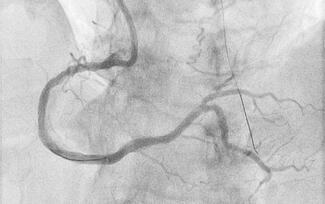

A 63-year-old man with stable angina was scheduled for elective percutaneous coronary intervention of a chronic total coronary occlusion of the right coronary artery (RCA) with epicardial bridging collaterals from the left circumflex artery...